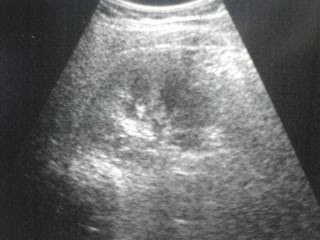

2)超音波検査(心臓・腹部)の正常画像・疾患画像 小池医院. 写真左側が腎臓、右側が脾臓です。 腎臓はそら豆のような形をしているのが分かりますよね。 腎臓は、左右に一つずつ.